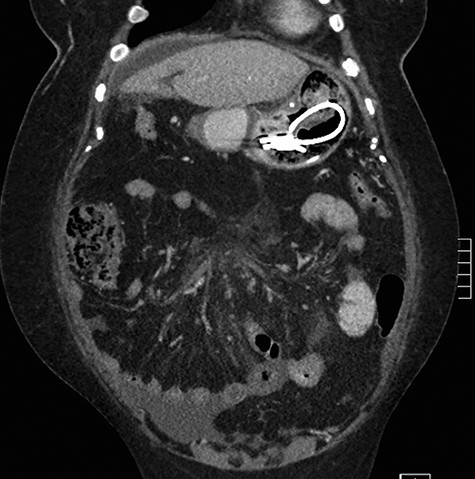

A 59-year-old female presented to the emergency department with a 2-week history of progressive central abdominal pain and distention on a background history of a laparoscopic adjustable band insertion 11 years previously. She had associated nausea, vomiting and denied dysphagia, odynophagia, or change in bowel habit. Clinically, she was afebrile, tachycardic, and on examination, displayed diffuse abdominal tenderness and guarding. Inflammatory markers were mildly elevated (white cell count 13.7 × 109/L, C-reactive protein 105 mg/L), and a moderate hyperlactatemia was observed (lactate 2.4 mmol/L). A plain film abdomen demonstrated a distended, air-filled stomach (Fig. 1). Subsequent computed tomography of the abdomen and pelvis demonstrated an intragastric band erosion with the internalization of the entire gastric band and distal connector tubing within the gastric lumen (Fig. 2). Moderate free fluid and ascites were noted with considerable mesenteric inflammatory fat stranding. The portal vein was non-opacified, indicating a possible portal vein thrombosis (PVT).

The patient was promptly brought to the theater for an exploratory laparotomy. Approximately 30 cm of ischemic small bowel segment with engorged mesentery was identified and resected; while doing so, blood clots were extruding out of the mesenteric vascular arcade. An on-table OGD was performed, demonstrating a deformed shaped stomach. The gastric band had completely eroded through the wall of the stomach. A biofilm had formed around the band device from the distal connecting tubing, tracking into the fundus of the stomach and sealing the perforation (Fig. 3). The biofilm was tracked to the stomach externally, the stomach opened and the device retrieved (Fig. 4). The stomach was closed in two layers and abdominal drains were inserted prior to closure.